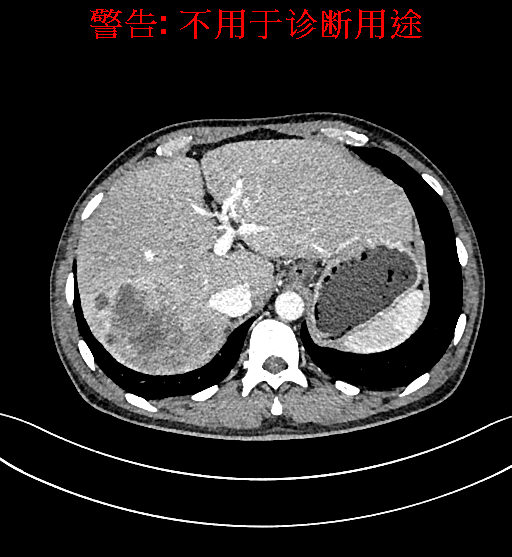

上腹部增强CT示肝右叶多发低密度结节、片团影伴肝门区、肝胃间隙多发肿大淋巴结,原发性肝Ca可能性大,请结合临床肝硬化肝脏小囊肿。

术前CT检查:

动脉期